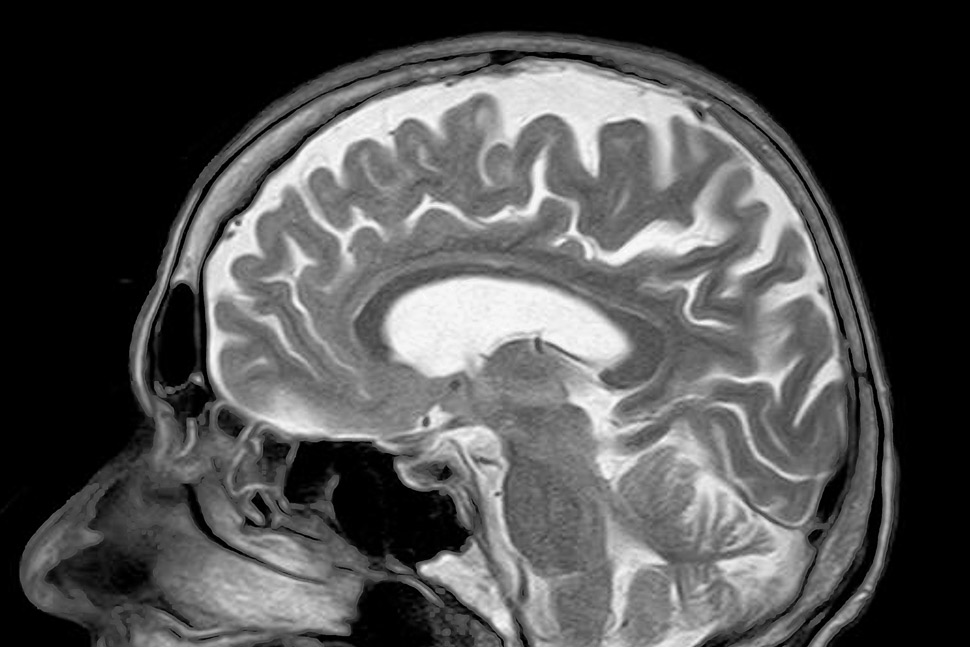

Niniejszy projekt ma na celu zbadanie uwarunkowań neurobiologicznych i psychologicznych czynów pedofilnych. Podjęta zostanie próba analizy procesów poznawczych i emocjonalnych w grupie sprawców tego rodzaju przestępstw. Uwzględnione zostaną zarówno świadome, jak i nieświadome aspekty kontroli zachowania, podejmowania decyzji oraz zdolności do rozpoznawania emocji i stanów psychicznych innych osób. Jednocześnie, z wykorzystaniem metody rezonansu magnetycznego, poszukiwane będą neuronalne mechanizmy tych procesów.